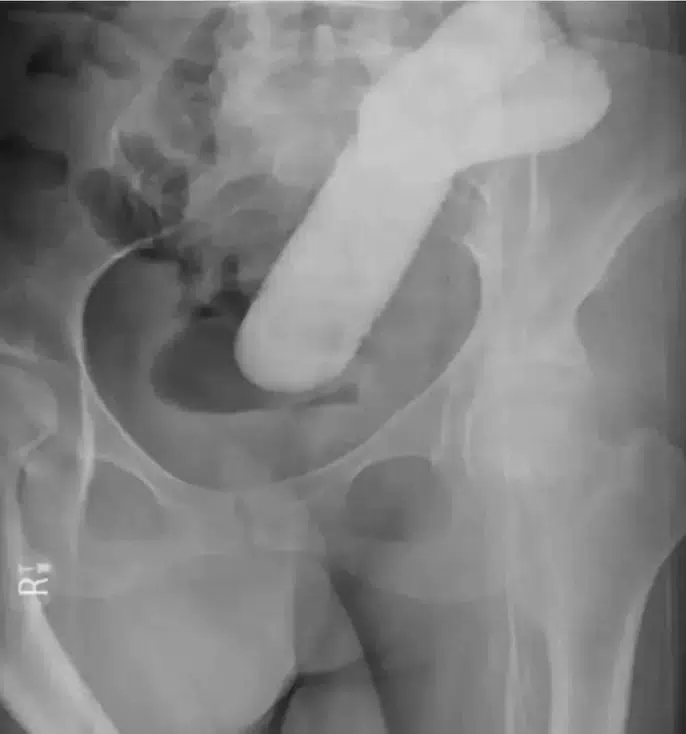

Il sex toy, una volta inserito, è rimasto incastrato nel retto dell’uomo e ha continuato a funzionare, causandogli dolori lancinanti. Non solo, ma l’oggetto si è spinto molto più in alto del previsto, rendendo la situazione ancora più delicata e pericolosa.

Nonostante la situazione sia alquanto insolita, non è la prima volta che un sex toy causa problemi simili. In passato, ci sono stati casi di giocattoli erotici che si sono incastrati nel retto di altre persone, causando situazioni altrettanto pericolose. Ad esempio, alcuni mesi fa, una donna è finita in ospedale per lo stesso motivo. Il sex toy si era bloccato nel colon, causando un’ostuzione intestinale potenzialmente pericolosa. Questo episodio aveva richiesto un intervento chirurgico d’urgenza per rimuovere il giocattolo, che rappresentava una riproduzione di un grande pene con testicoli annessi, inserito al contrario.